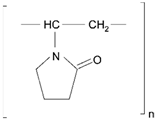

| Polyvinyl pyrrolidone (PVP), poly (N-vinyl pyrrolidone) |  | Sol-gel/solvent casting | Cytarabine, ara-ADA, Polyscience | Superior biocompatibility, has suspension capabilities, antinucleating agent, and enhances release rate | [163] |